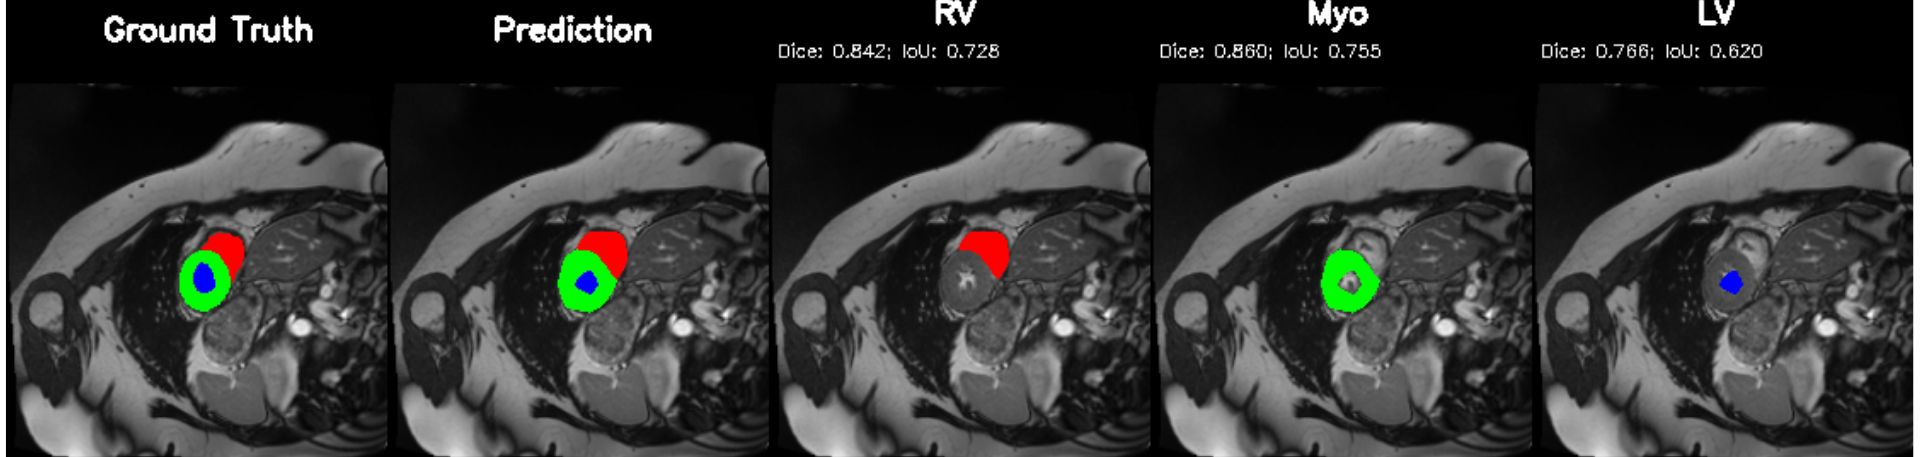

5.2 M&Ms Cine-MRI Generalization

Figure 8 illustrates segmentation outputs on the M&Ms (Multi-Centre, Multi-Vendor) cine-MRI dataset, which exhibits both contrast variation and vendor–specific acquisition differences compared to ACDC. The model retains consistent ventricular geometry, recovering LV and Myocardium structure without retraining, mirroring the zero-shot Dice performance of 74.8% (Table 11). Boundary thickness remains physiologically accurate, with only minor degradation in the right ventricle, an expected behaviour under cross-domain shifts and also reflected quantitatively in the ablation-driven robustness improvements from normalization and loss design. These results demonstrate that PULSE does not overfit to a single scanner distribution but instead transfers cardiac structure priors across unseen clinical environments.